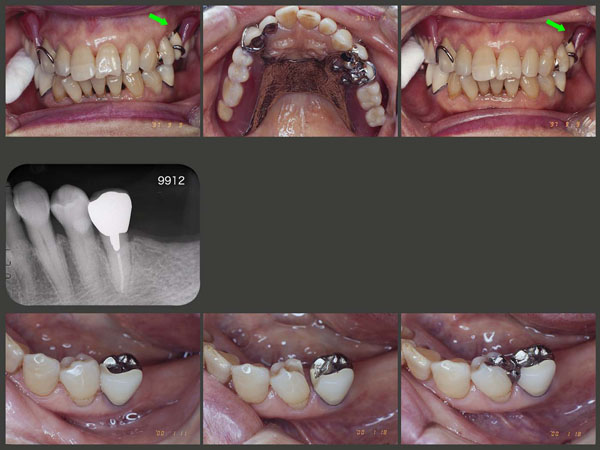

右上の人工歯部でロールワッテを咬んでもらうと,スライド左上では,反対側が浮き上がっているに対して,調節が終了したスライド右上では,その浮き上がりが減少しているのが見てとれる.(緑矢印の部分)